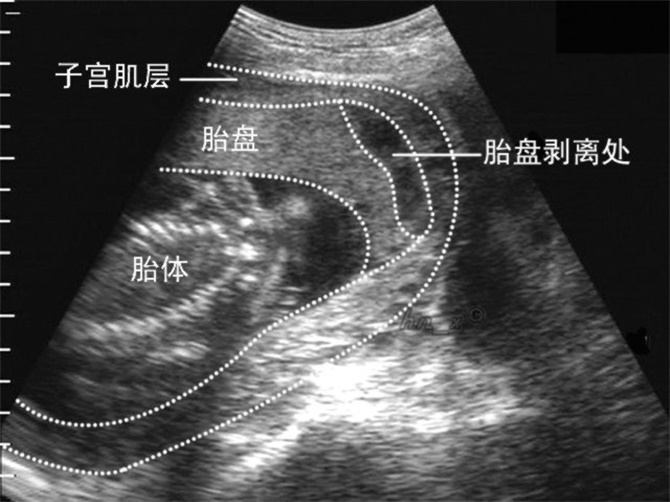

邊緣性胎盤早剝

胎盤早剝超聲診斷

胎盤早剝腹痛症狀